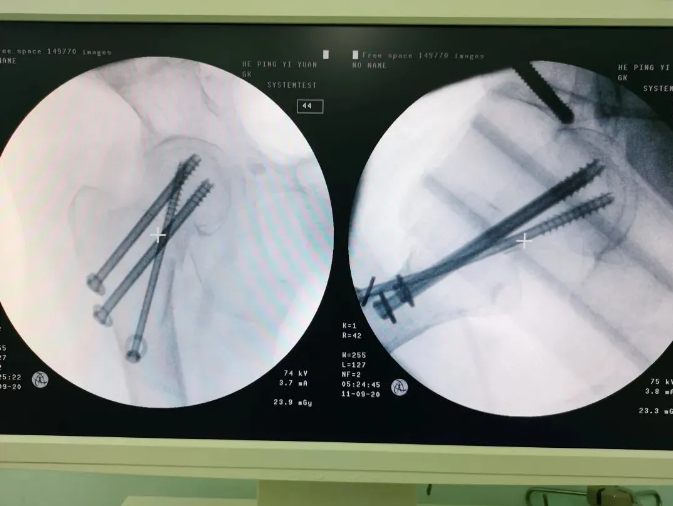

Ììçá»úеÈËÖÃÈëÂݶ¤

Âݶ¤ÖÃÈëºó